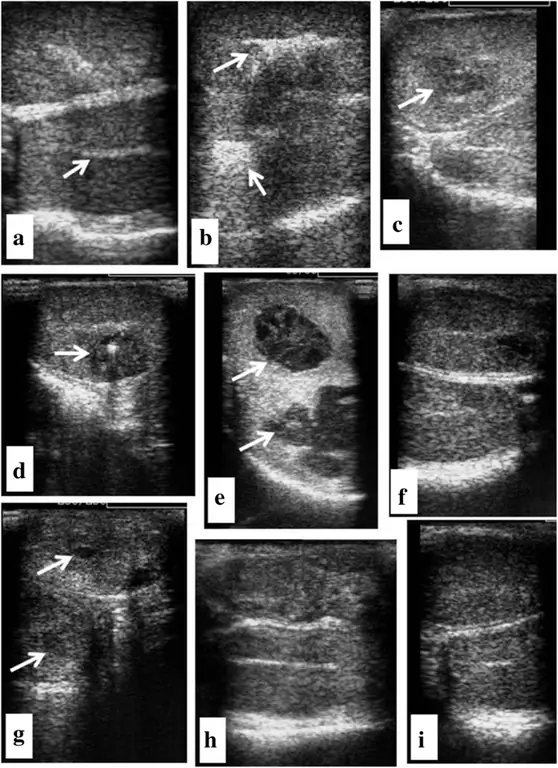

фигура 1

Ультразвуковое исследование яичек до (а) и 0 (б), 3, (с), 6 (д), 12 (е), 21 (ж), 28 (г), 35 (ч) и 37 (и) дней после введения глюконата цинка. перед инъекцией стрелка указывает на повторное яичко; b гиперэхогенная эхотекстура указывает на введенный раствор глюконата цинка (стрелка); стрелки c, d, e, g указывают на образование и удаление кистозоподобных структур; ч, я ультразвуковое исследование яичек в конце исследования (день 37)

Жизненные показатели регистрировали до и после лечения два раза в день, чтобы быть в пределах нормы. Одна из собак укусила левое яичко, что вызвало ранение и привело к образованию абсцесса. Через 2 недели абсцесс разорвался и зажил в течение 5 недель. В конце исследования оба яичка были нормальными и без воспаления. Отек яичек был очевиден у двух собак через 1-2 дня после инъекции и затем постепенно уменьшался в течение 3 недель после лечения. На 37 день после инъекции оба яичка были в норме и без воспаления. У одной из собак при использовании ультразвука в обоих яичках наблюдалась структура, напоминающая абсцесс, которая впоследствии со временем уменьшалась в диаметре и не была обнаружена к концу исследования (Рис. 1c, d, e, g, h, i).,